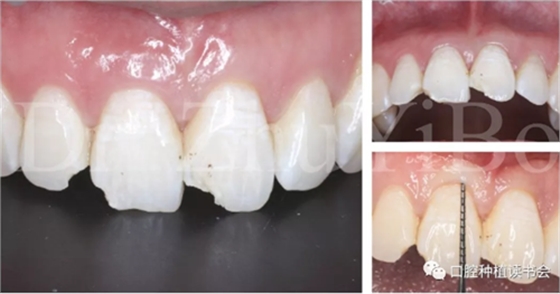

4.2.5 雙區(qū)植骨,戴牙(圖14,圖15)。

圖14 雙區(qū)植骨需要植到齦緣水平

圖15術(shù)后即刻CBCT示:種植體軸向及深度良好

圖16 即刻修復(fù)后,患者恢復(fù)了美觀